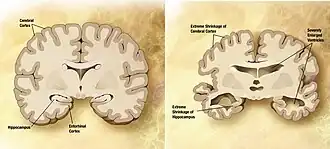

Dementia becomes more common with age.[47] About 3% of people between the ages of 65 and 74, 19% of those between 75 and 84, and nearly half of those over 85 years old have dementia.[48] The spectrum ranges from mild cognitive impairment to the neurodegenerative diseases of Alzheimer's disease, cerebrovascular disease, Parkinson's disease and Lou Gehrig's disease. Furthermore, many types of memory decline with ageing, but not semantic memory or general knowledge such as vocabulary definitions. These typically increase or remain steady until late adulthood [49] (see Ageing brain). Intelligence declines with age, though the rate varies depending on the type and may, in fact, remain steady throughout most of the human lifespan, dropping suddenly only as people near the end of their lives. Individual variations in the rate of cognitive decline may therefore be explained in terms of people having different lengths of life.[50] There are changes to the brain: after 20 years of age, there is a 10% reduction each decade in the total length of the brain's myelinated axons.[51][52]